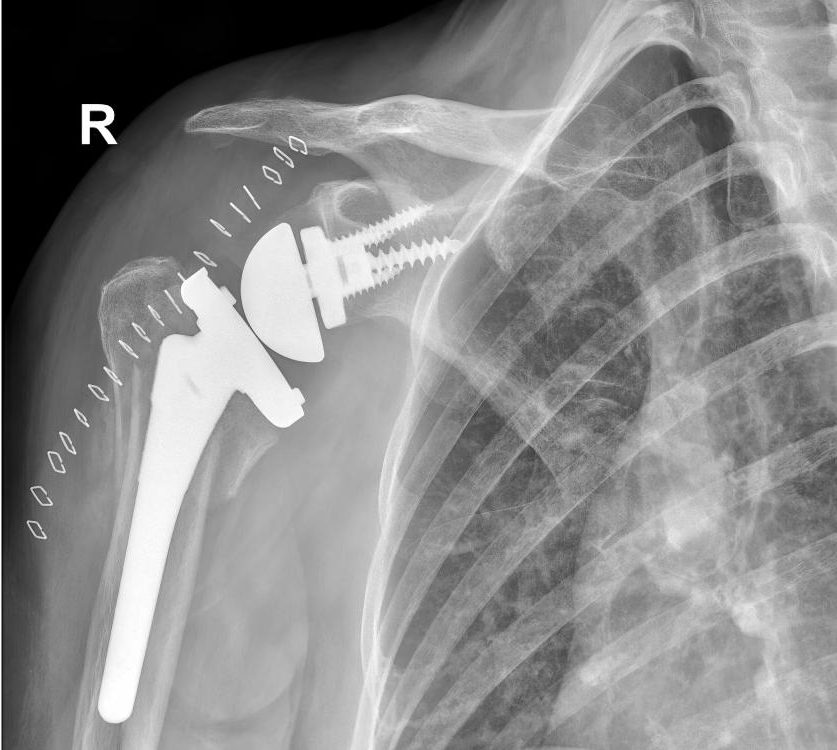

The researchers identified other risk factors for readmission as well. Patients admitted for urgent shoulder surgery — rather than a scheduled procedure — were 65% more likely to be readmitted within 30 days. Those who received a reverse shoulder replacement — where the socket is affixed to the humerus, and the ball is on the shoulder joint — were 36% more likely to be readmitted. Patients who had one or two other significant medical conditions — like heart disease or diabetes — were 52% more likely to be readmitted, while those with three or more such conditions were 148% more likely to need to return to the hospital.